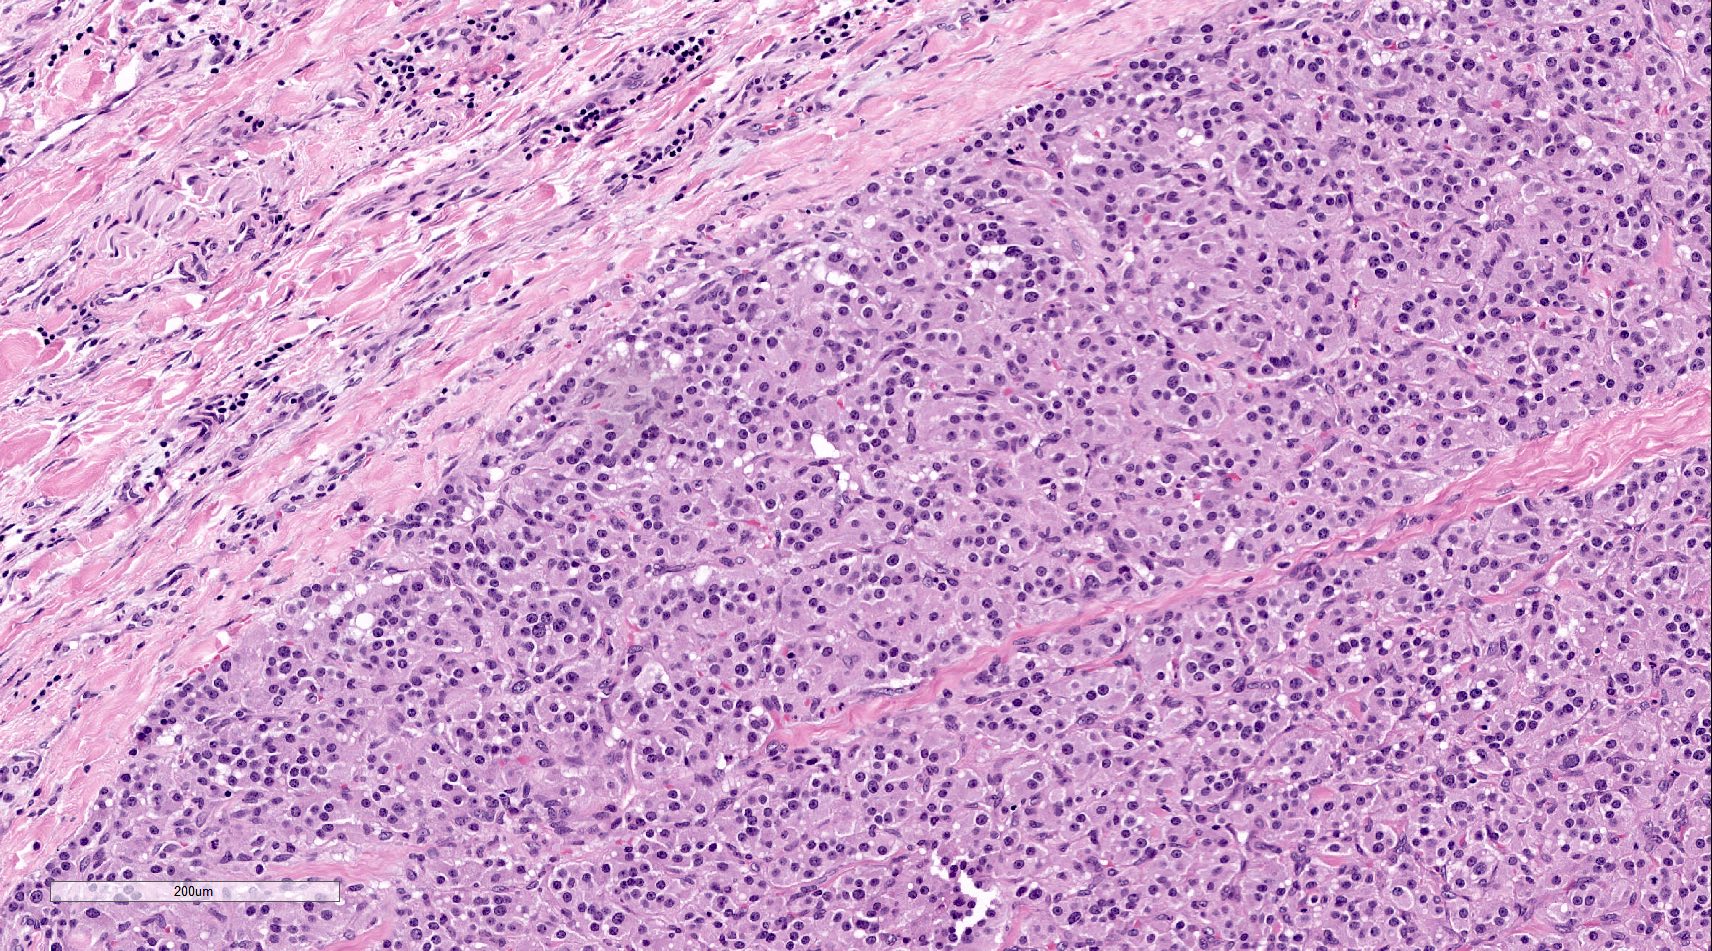

Microscopic (histologic) description

- Prevailing histologic pattern: epithelioid chief cells arranged in distinctive clusters / nests (zellballen pattern), separated by prominent fibrovascular stroma (J Clin Med 2018;7:280)

- Trabecular pattern: ribbons or cords of epithelioid cells divided by fibrous bands

- Other patterns: pseudorosette, angioma-like, spindled and sclerosing

- Chief cells: round, oval to polygonal cells with abundant granular basophilic, eosinophilic or amphophilic cytoplasm (Surg Pathol Clin 2019;12:951)

- Intracytoplasmic hyaline globules may be present in sympathoadrenal paragangliomas

- Giant multinucleated cells and bizarre cells can be present (Srp Arh Celok Lek 2002;130:7)

- Rarely, elongated and spindle shaped cells with a sarcomatoid appearance may be found

- Scattered ganglion cells can be seen

- May have nuclear atypia

- May have dysmorphic vessels, melanin-like pigment (neuromelanin) (pigmented paraganglioma), amyloid, abundant stroma and osseous metaplasia (Diagn Pathol 2012;7:77, Hum Pathol 1992;23:33)

- No or rare mitotic figures except in highly aggressive rapidly proliferating lesions

- May have focal chronic inflammatory infiltrate

- Necrosis is unusual except in patients who have undergone preoperative tumor embolization

- Special histopathologic features usually related to genetic syndromes:

- VHL syndrome: prominent stromal edema, clear cytoplasm and lipid degeneration (Am J Surg Pathol 1987;11:480)

- SDHx related syndrome: granular eosinophilic cytoplasm (Am J Surg Pathol 2020;44:422)

- MEN2 syndrome: unilateral or bilateral adrenal medullary hyperplasia (Neoplasia 2014;16:868)

Microscopic (histologic) images

Contributed by Luvy Delfin, M.D. and Sylvia L. Asa, M.D., Ph.D.